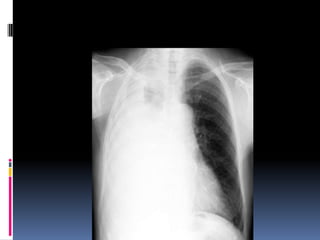

Underpenetrated Film

Hemi diaphragms are obscured

Pulmonary markings more prominent than they actually

Over penetrated Film

 Lung fields darker than

normal—may obscure subtle

pathologies

•   See spine well beyond the

diaphragms

•   Inadequate lung detail